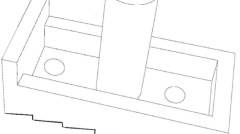

一种椎间融合器成果简介

发布:中医药创新转化研究院